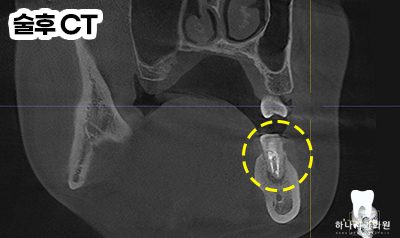

우선 CT 촬영 후 사진에서 보았을 때

원심 근관의 충전을 보면 중앙을

충전물이 지나지 않는 것을

확인할 수 있었습니다.

모든 근관은 치근의 중앙을 지난다는

원칙에 위배되어 하나의 근관이

더 있다는 결론을 도출할 수 있었는데요.